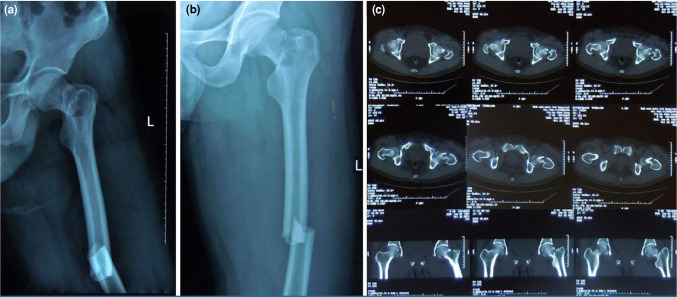

Patients and methods: Between January 2013 and December 2021, a total of 25 adult patients (19 males, 6 females, mean age: 32.8±10.9 years; range, 19 to 57 years) who sustained concurrent ipsilateral femoral neck and shaft fractures were included. The patients underwent internal fixation using a reconstruction nail with the assistance of a reductor-T tape pin, employing percutaneous techniques. The operation time, reduction time, fluoroscopy time, blood loss, preoperative and postoperative Visual Analog Scale (VAS) scores, fracture union time, Harris scores of the healthy and affected sides after fracture union, complications and lower limb functional outcomes two years post-surgery were recorded.

Results: All patients underwent successful surgery with the assistance of the reductor-T tape pin using percutaneous techniques without the need for open reduction. The mean operation time from skin incision to wound closure was 80.0±15.0 (range, 55 to 105) min. The mean fracture reduction time was 22.0±4.0 (range, 15 to 28) min. The mean fluoroscopy time was 16.0±3.8 (range, 9 to 25) sec. The mean blood loss was 335.0±142.0 (range, 150 to 550) mL. The postoperative VAS score of the affected limb was significantly lower than the preoperative score (p<0.01). The mean healing time of femoral neck fractures was 4.0±0.3 (range: 3.2 to 4.8) months. The mean healing time of femoral shaft fractures was 4.8±0.9 (range, 4.1 to 7.5) months. All patients were followed for over two years. No cases of delayed healing of femoral neck fractures or femoral head necrosis were observed. However, delayed union of femoral shaft fractures occurred in three patients. There was no statistically significant difference in Harris scores between the affected and healthy sides at the time of fracture healing (p>0.05).

Conclusion: The use of a reconstruction nail assisted by the percutaneous reductor-T tape pin demonstrated successful reduction of ipsilateral femoral neck and shaft fractures, with favorable postoperative functional outcomes. The reductor-T tape pin facilitates the reduction of femoral neck fractures and provides a safe environment for the reduction and fixation of femoral shaft fractures.